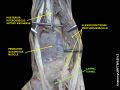

Wrist joint. Deep dissection.Anterior, palmar, view.

-